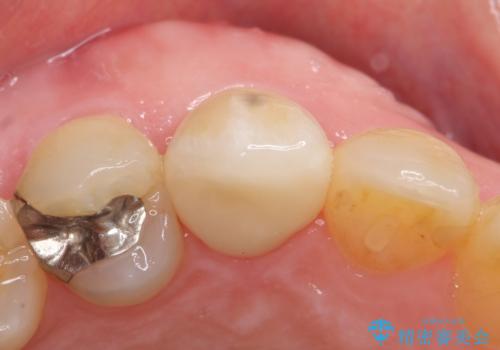

- 他院にて根管治療を行ったが疼きが治まらないため、当院にいらっしゃった方の症例です。

再根管治療を行い症状が治まったのを確認後、オールセラミッククラウン(スペシャル)による補綴を行いました。

- オールセラミッククラウン(スペシャル)…¥130,000、仮歯…¥10,000、ファイバーコア…¥20,000、精密根管治療費別途費用は治療当時の料金となります